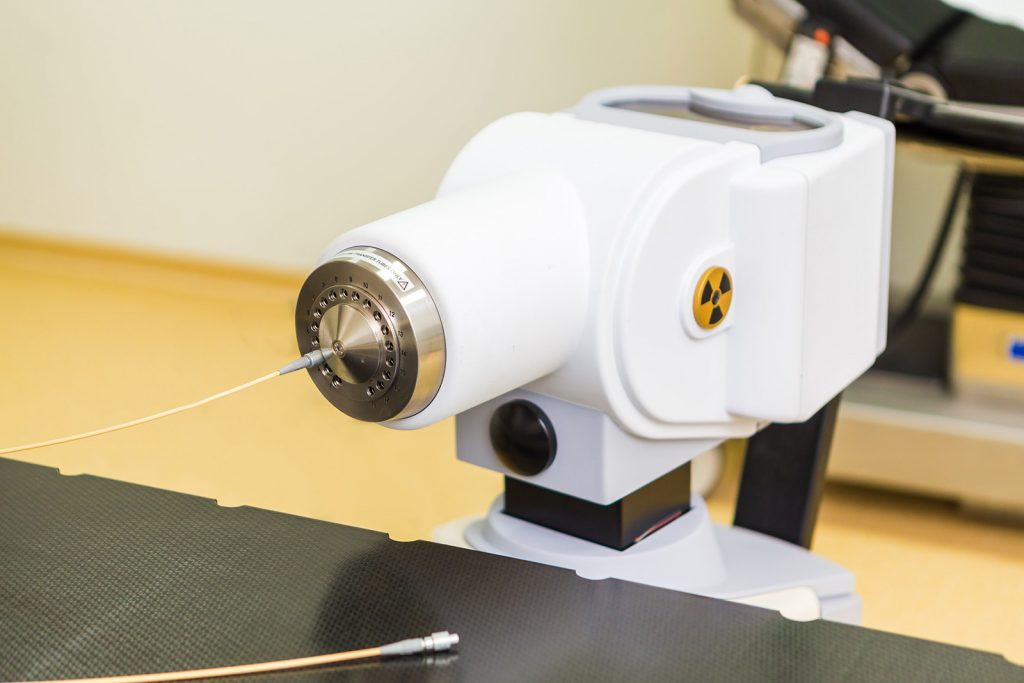

Brachytherapie

Bei dieser Methode werden eine oder mehrere radioaktive Quellen in tumorbefallene Hohlorgane eingesetzt oder mittels Nadeln direkt in den […]